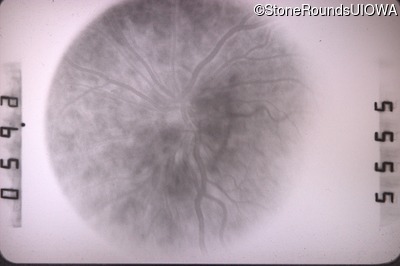

Fluorescein Angiography - Right - 20/50 +2

Exemplar